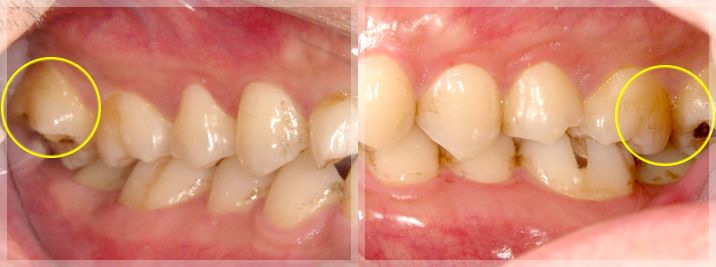

初診時

左の写真:咬合平面の乱れ|右の写真: 晩期残存乳歯

左右の写真:すれ違い咬合

晩期残存乳歯の改善

術前 | 術後 |

すれ違い咬合の改善